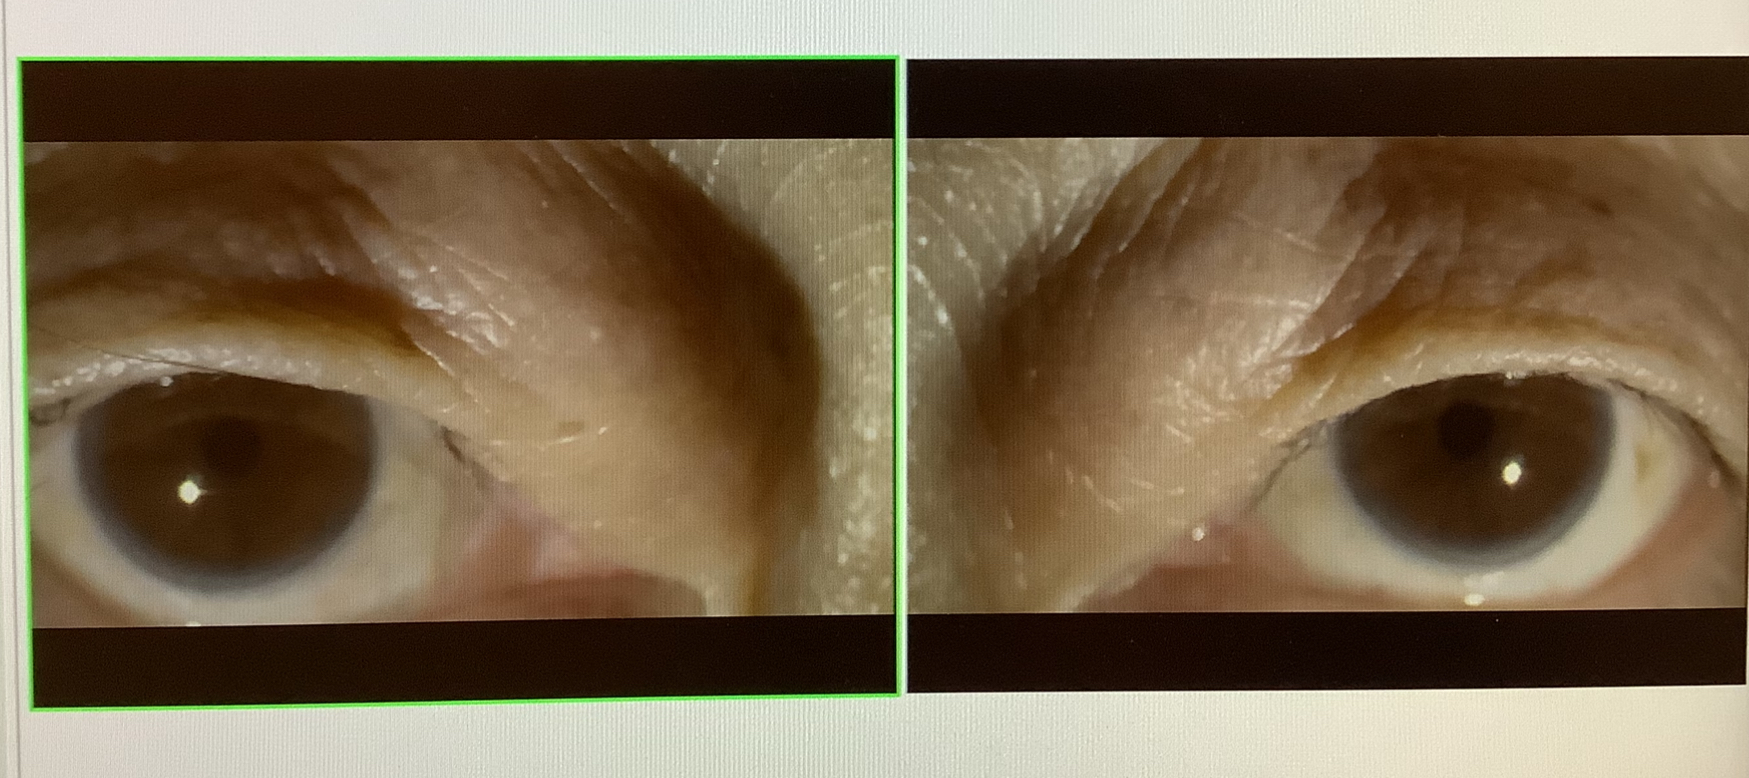

まぶたの手術の前に、1件、処置が追加になりました。昨日の白内障の手術の患者さまで白内障の濁りの塊(核片)が少しだけ眼の中に残ってしまっていたので、前房洗浄で残った核片を吸い取らせていただきました。追加の処置になってしまって申し訳ありませんでしたが、水晶体が眼の中に残ると、炎症を引き起こしてしまうことがありますし、翌日であれば、傷口も簡単に開くので新たに余計なキズを作らないで済むので早めの処置がよいと判断しました。連日の手術、処置となってしまい、すみませんでした、、、